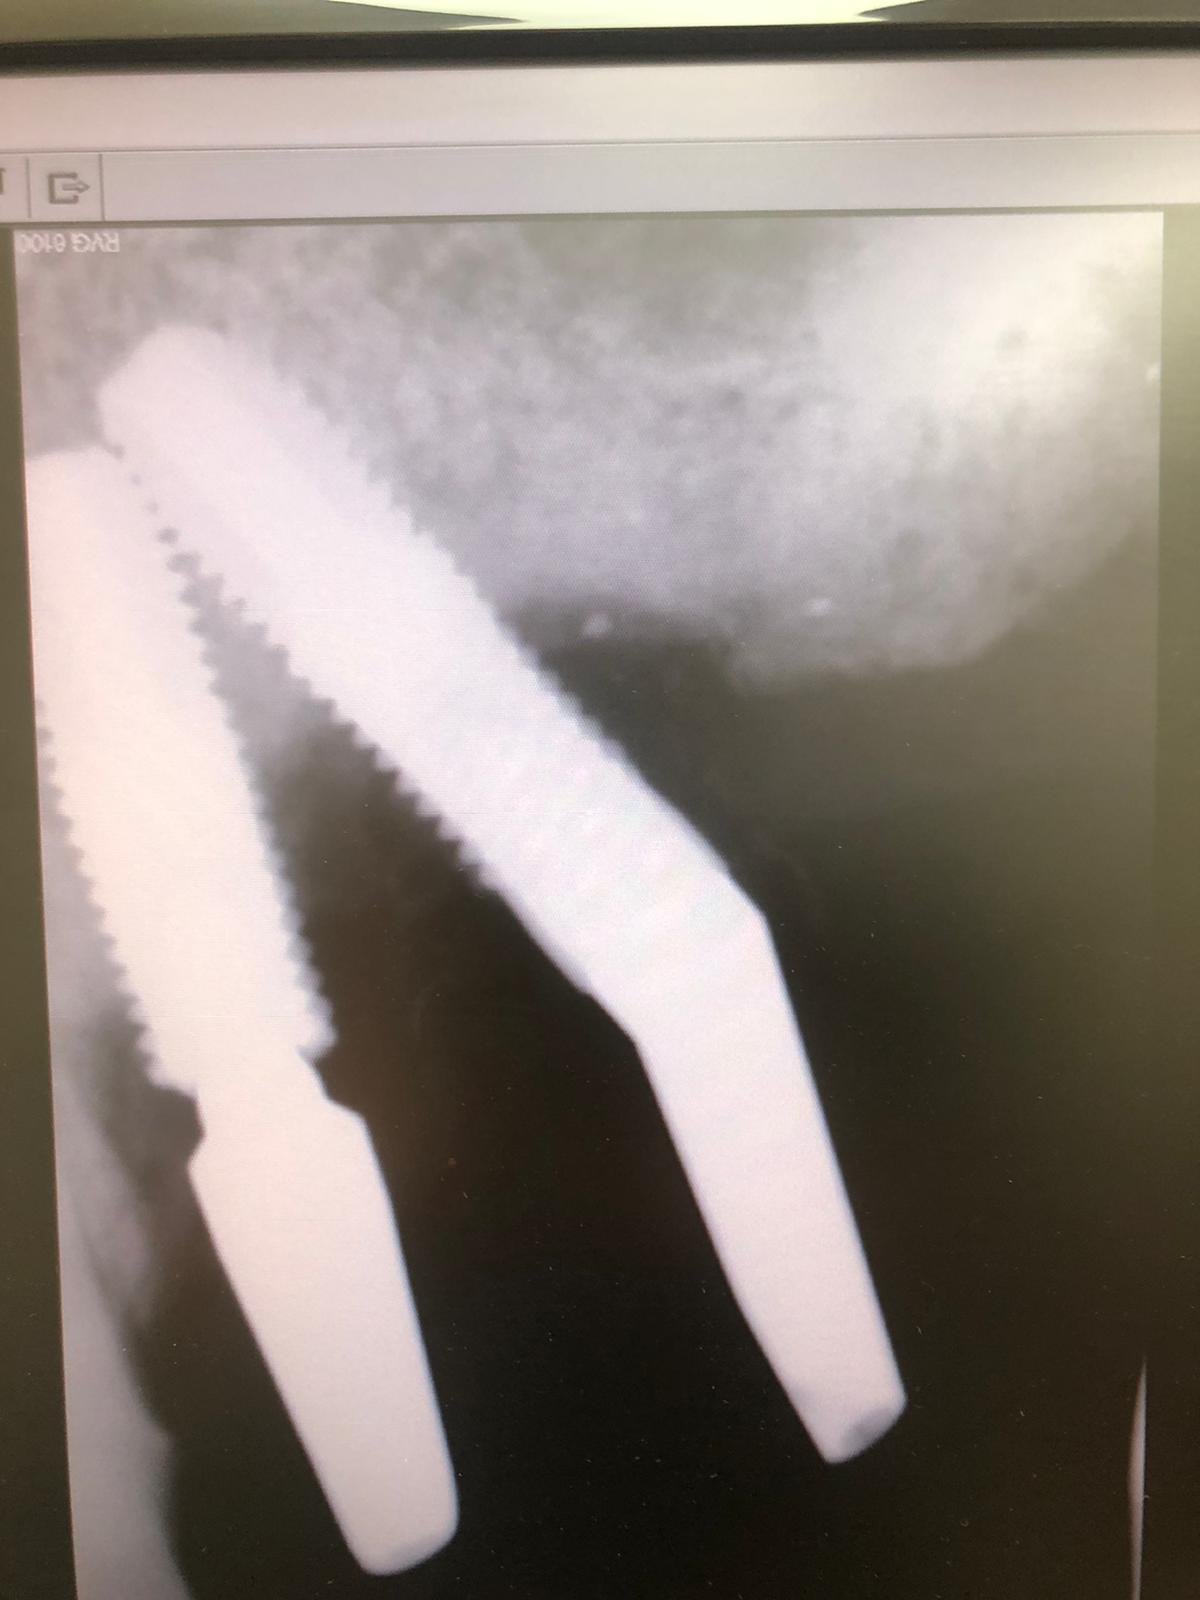

La solución a este caso fue rehacer la rosca distal rota (un poco inclinada) y después seleccionar, sellar y tallar el aditamento ASATIM. Con la sucesión de imágenes se comprende cómo se rehace una rosca:

La flecha negra es la posición rotacional: 0 grados del aditamento tanto en la caja Asatim como el aditamento que está instalado en el implante. Hemos de seleccionar otro aditamento que su posición rotacional esté siguiendo la flecha verde y este ha sido un aditamento de posición rotacional: 60 grados: Este aditamento angulado que la parte angulada está mirando hacia Mesial (POSICIÓN ROTACIÓNAL: 60grados) es el correcto.

Posteriormente lo sellamos con un cemento resínico. Y ya nos queda tallar. En cuanto cicatrice la encía podremos tomar impresión para la prótesis. Esperemos que resistan una temporada larga.